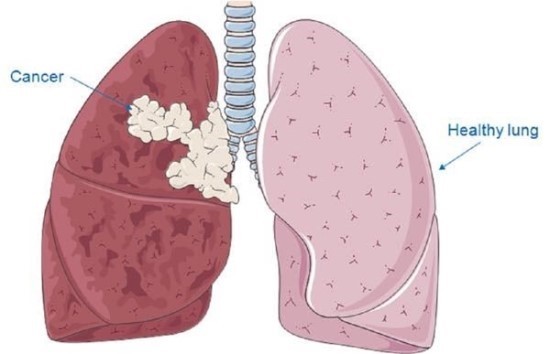

폐암은 위암, 갑상선암 다음으로 3번째로 발병 빈도가 높은 3대 암 중 한 가지인데요. 폐암은 재발과 전이까지의 빈도도 잦은지라 완치가 어렵다고 하며 폐암 발병 초기에는 거의 증상이 없을 수가 있어 수술이 불가능한 3기, 혹은 4기에 주로 진단된다고 해요.

폐암 초기 증상으로 호흡곤란 증상이 있어요. 폐에 문제가 생기니 당연히 숨이 찰 수밖에 없어요. 평상시 조금만 걸어도 숨이 아주 차거나 심하게 가빠지는 등의 호흡에 문제가 발생하게 돼요. 폐에 암세포가 커지기 시작하게 되면 폐허탈, 흉막삼출 등의 질환으로 인해 극심한 호흡곤란을 느끼기도 해요.

9. 흉부 고통

폐암에 걸리면 흉부에 고통이 느껴져요. 폐의 가장자리에 생긴 폐암이 흉막과 흉벽을 침범해서 고통이 생기는 것으로 가슴이 답답하면서 꽉 막힌 느낌이 지속되며 날카롭게 찌르는 듯한 느낌과 압력 하는 느낌 등 여러 가지 고통이 나타납니다.